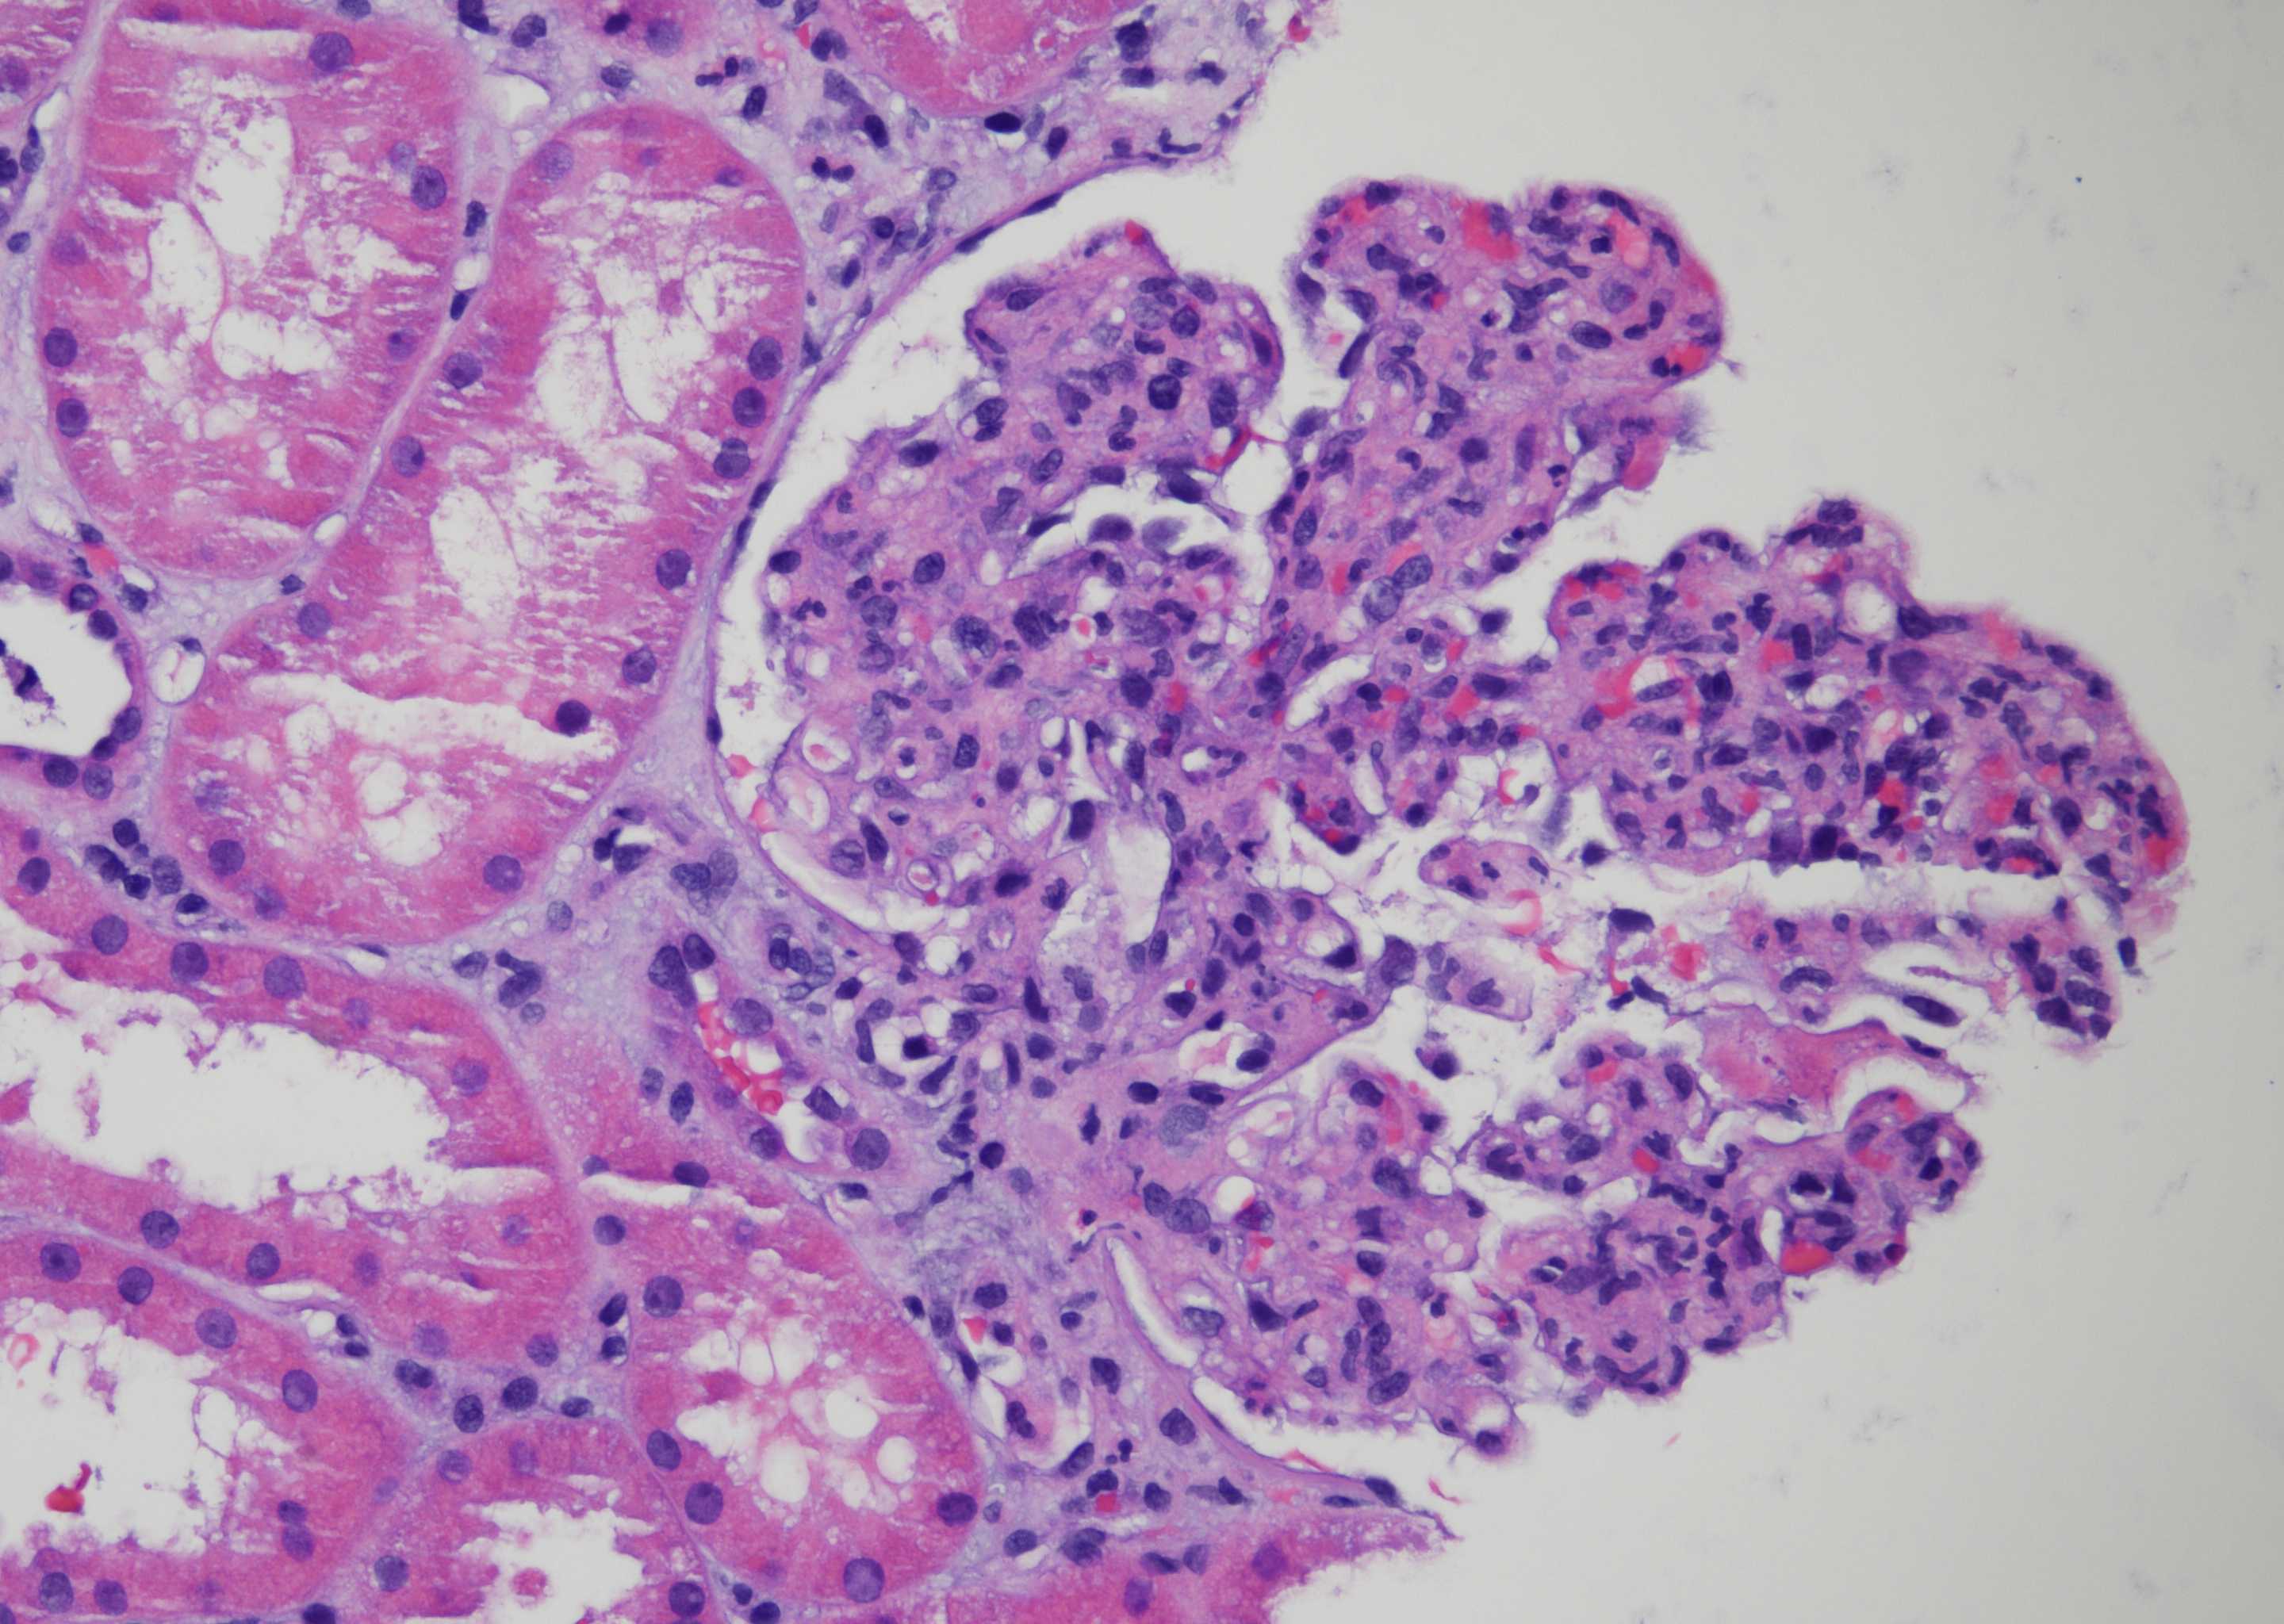

Results: Work up was notable for bartonella henselae bacteremia. He underwent an allograft biopsy that demonstrated post-infectious glomerulonephritis (GN); Mycophenolate was discontinued and treatment was started with rifabutin and doxycycline. AKI initially improved, but later worsened and a second biopsy was performed, which revealed a pattern of diffuse suppurative proliferative GN (Fig.1) with focal crescents (Fig. 2). Electron microscopy revealed sub-endothelial and sub-epithelial electrondense immune deposits. The immune deposits were predominantly IgA, IgM and C3, and negative for IgG. He was started on IV steroid pulse and initiated on dialysis for worsening volume overload. Four weeks after discharge a follow-up biopsy was performed as the patient remained on dialysis. The biopsy showed a focal proliferative GN with more segmental intra-membranous immune deposits and rare sub-epithelial humps, a pattern consistent with resolving post-infectious GN. Soon after he came off dialysis with resolving acute kidney injury.